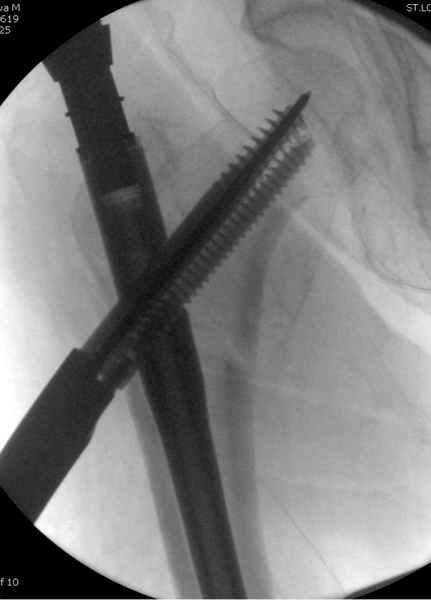

Мы получили испытательный вариант инструментария для пробы, хотя компания объявила, но ещё не для широкой публики, обещают к сентябрю. За полтора месяца, включая сегодняшнюю, вот уже восьмая операция по счету. Удобный инструментарий, ничего лишнего, научились делать быстро, посмотрим что будет, пока нравится.

Здесь сканнированные снимки импланта и операционные снимки больной.

На этом снимке процесс компрессии нижним болтом.